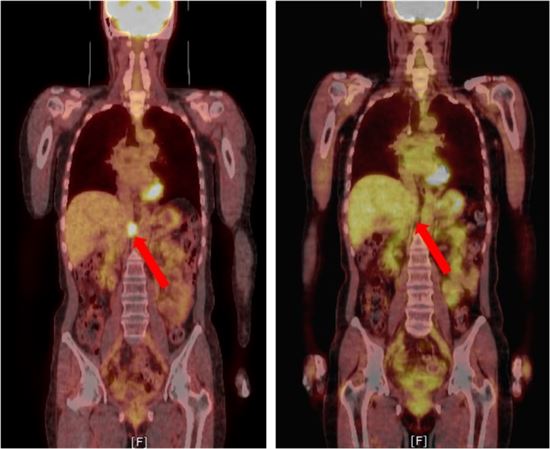

정위신체방사선치료는 3차원 좌표계를 적용해 암세포의 위치와 모양을 계산하고 정확히 정렬한 뒤 고선량의 방사선을 여러 방향에서 암세포에 집중적으로 쏘는 방사선치료법이다.

김미숙 박사팀은 지궁경부암, 대장암, 위암, 간암 환자들 중 복부 임파절에 5개 미만의 전이된 종양이 발견된 환자 88명을 대상으로 환자의 상태에 따라 76명의 환자에게는 3~5회, 12명의 환자에게는 1~3회의 방사선치료를 시행했다. 치료결과 5년 간 치료부위에서 더 이상 암이 생겨나지 않는 환자가 83%, 5년 간 재발이 없이 완치 된 무병 생존자가 31%로 나타났다. 대상 환자들의 5년 전체 생존율은 41%였다.

정위신체방사선치료는 기존의 일반적 방사선치료에 비해 주변 정상조직의 손상은 최소화하면서 암세포만 칼로 도려내는 것과 같은 원리의 치료방법이다. 첨단 방사선수술로 크게 각광받고 있다. 2002년 이후 현재까지 약 3000명 이상의 정위신체방사선치료를 시행해 온 한국원자력의학원은 2012년부터 관련 치료기술을 국제원자력기구(IAEA)와 공동으로 아시아태평양 지역 16개 국가에 보급하고 있다.